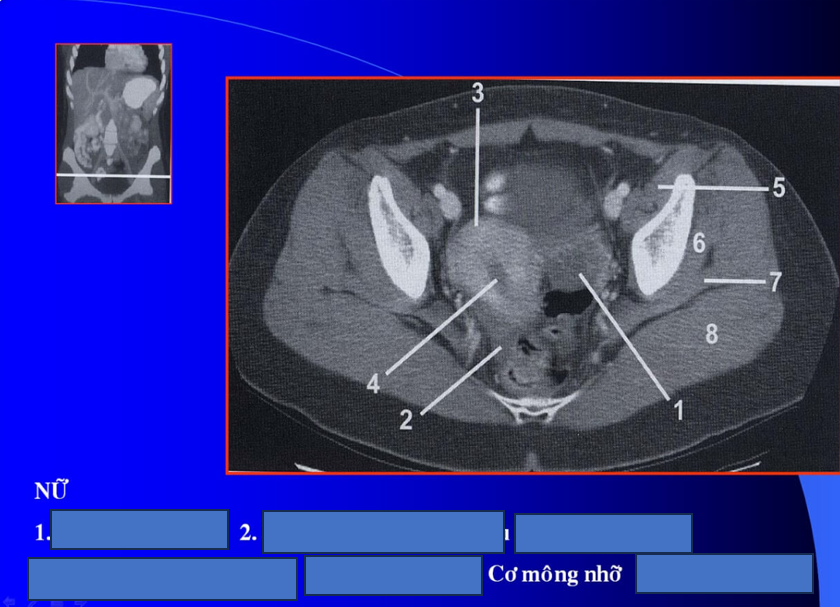

manh tràng? x cùng?